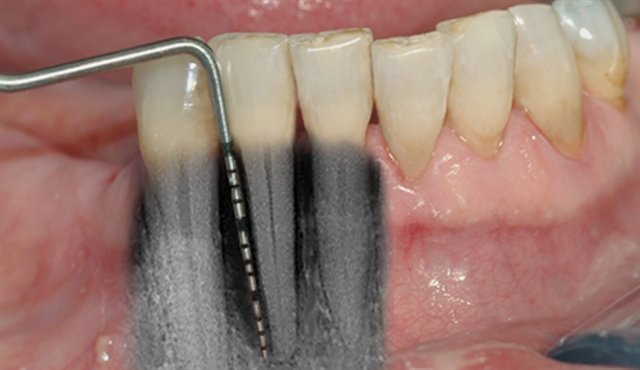

Bildet viser tilsynelatende normale tannkjøttsforhold ved tenner i underkjeven.

• perio stor 2

perio stor 2

En undersøkelse med lommeregistrering avdekker likevel et omfattende bentap ved den ene tannen.